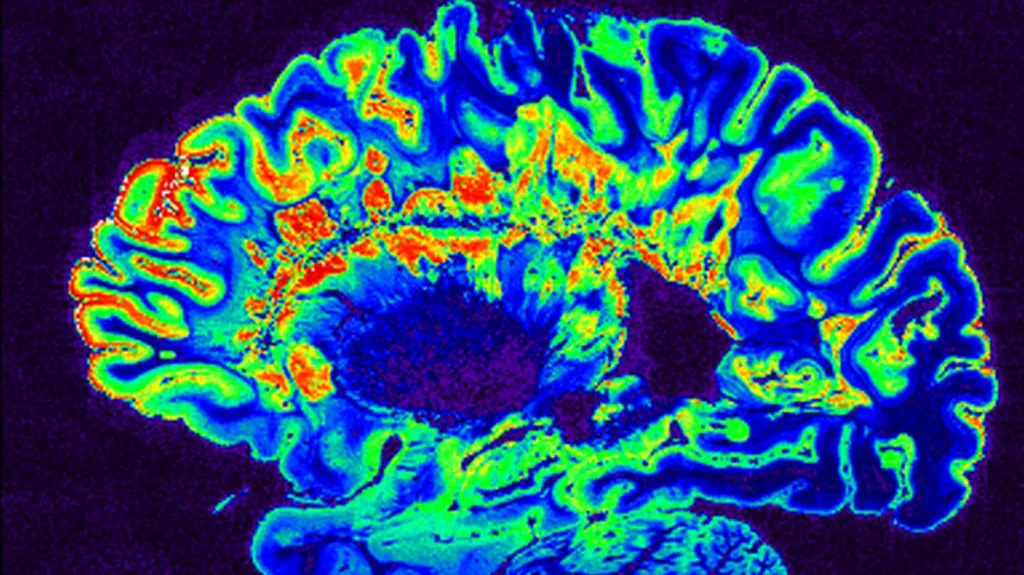

Krátkodobé výpadky pozornosti jsou běžným problémem u lidí s nedostatkem spánku. Vědkyně se proto zaměřily na procesy, které se v takové situaci odehrávají v mozku. Skeny orgánu odhalily vlnu mozkomíšního moku, která z něj byla vypuzena okamžitě po poklesu pozornosti a vrátila se asi sekundu po skončení ztráty pozornosti. Takové vlny se obvykle vyskytují v hlubokém spánku a předpokládá se, že pomáhají mozku vyplavit metabolické odpady, které se během dne hromadí.

„V okamžiku, kdy někdo ztratí pozornost, začne tato vlna tekutiny pulzovat,“ uvedla hlavní autorka studie Laura Lewisová. „Nejde jen o to, že vaše neurony nevěnují pozornost okolnímu světu, ale zároveň dochází k velké změně v mozkomíšním moku,“ vysvětlila expertka.